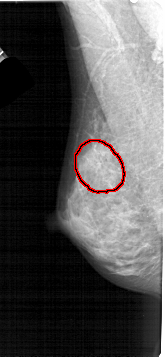

A_1446_1.LEFT_MLO

LEFT_MLO LINES 5341 PIXELS_PER_LINE 2461 BITS_PER_PIXEL 12 RESOLUTION 43.5 OVERLAY

FILE: A_1446_1.LEFT_MLO.OVERLAY

TOTAL_ABNORMALITIES 1

ABNORMALITY 1

LESION_TYPE CALCIFICATION TYPE AMORPHOUS DISTRIBUTION SEGMENTAL

ASSESSMENT 2

SUBTLETY 3

PATHOLOGY BENIGN

TOTAL_OUTLINES 1

BOUNDARY